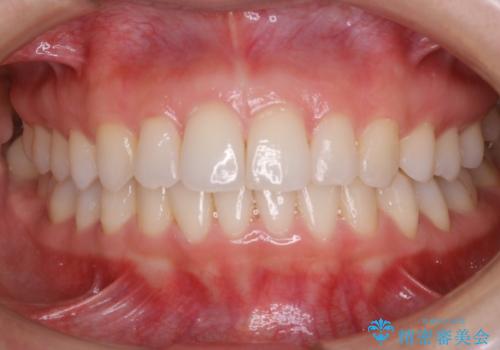

- 初診時、前歯部の見た目の改善を主訴にご来院されました。生まれつき歯が小さい状態の「矮小歯」とそれに伴う正中の「すきっ歯」があるため、大きなガタつきはないものの笑った時の印象に違和感が出る状態となっていました。

矮小歯が傾斜していることなどを踏まえ、より安全に治療を進めるために部分矯正を併用したセラミッククラウンでの治療を行うこととなりました。

今回のケースでは、歯が小さいだけでなく傾斜もしていたため補綴治療時に歯を削ることで神経の症状が出る可能性がありました。そのため、事前に部分矯正を行い歯軸の改善を行っておくことで、歯髄を温存することができました。